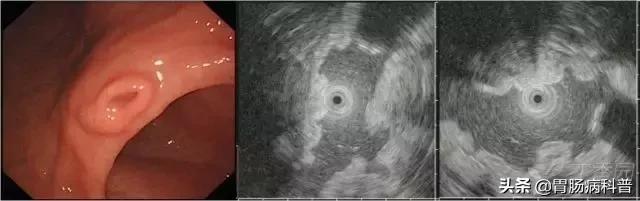

图 2胃神经内分泌瘤。

白光下胃体下前壁可见扁平黏膜下隆起,表面可见血管显露,EUS 下黏膜深层-黏膜下层可见低回声病变

图 3胃平滑肌瘤。

A 胃体小弯可见黏膜下隆起;B EUS 下固有肌层可见圆形、均匀低密度回声;C-D HE 可见梭形细胞,免疫组织化学可见α-SMA(+)